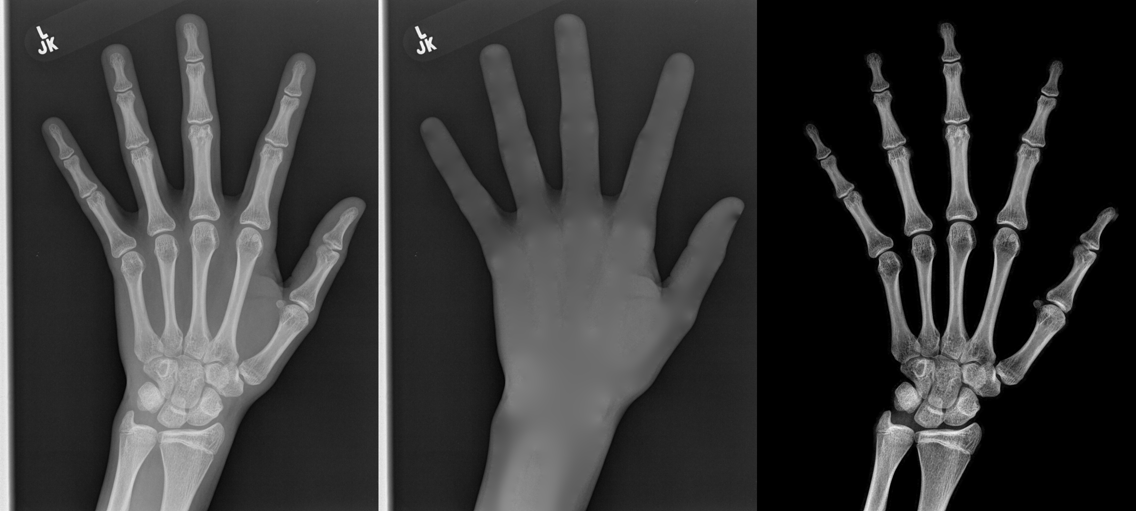

We performed three experiments for our method. First, we perform our method on several X-ray images, showing our method is not restricted by specific imaging objects. Second, we compared our method with image enhancement method and dehazing method, showing that our modification of the original dehazing indeed helps in this task. Third, we perform our method on a hand X-ray image dataset, showing its effectiveness and efficiency.

Several results from our method are shown in Fig. 7. The left column is the original input image. The right two columns are the soft tissue and bone image, respectively. It can be told that the soft tissue image is smooth as we assumed. Meanwhile, the bone image has better image contrast as desired. Moreover, our method can reach real-time performance on these X-ray images. The running time of our method on these images is reported in Table I.

In the third experiment, we applied our method on a hand X-ray image data set (RSNA), which contains more than 10,000 hand X-ray images. And the image has high resolution (usually larger than ). These images are collected from clinical applications. Therefore, we can apply our method on these practical images, showing the efficiency and effectiveness of our method on real high resolution images.

In each panel of Fig. 10, the input image (left) is decomposed into soft tissue (middle) and bone image (right) by our method. Although we only show the first ten images from the data set, the results for the rest images are similar.

The bone images have better image contrast since the parameter is theoretically guaranteed. Such enhancement can also be directly told by radiologists. Such enhancement is good for bone diagnosis in practical applications.